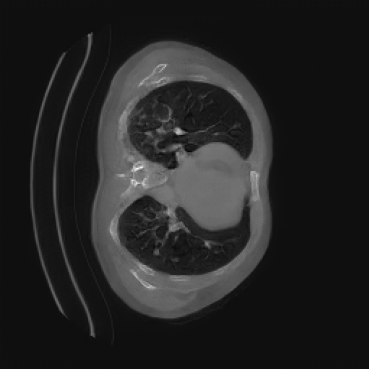

As shown in Figure 5, the generated slices exhibit high consistency across adjacent slices. The anatomical structures and semantic patterns are smoothly and coherently preserved between slices, indicating that our model is capable of generating 3D-consistent synthetic images rather than isolated 2D slices.